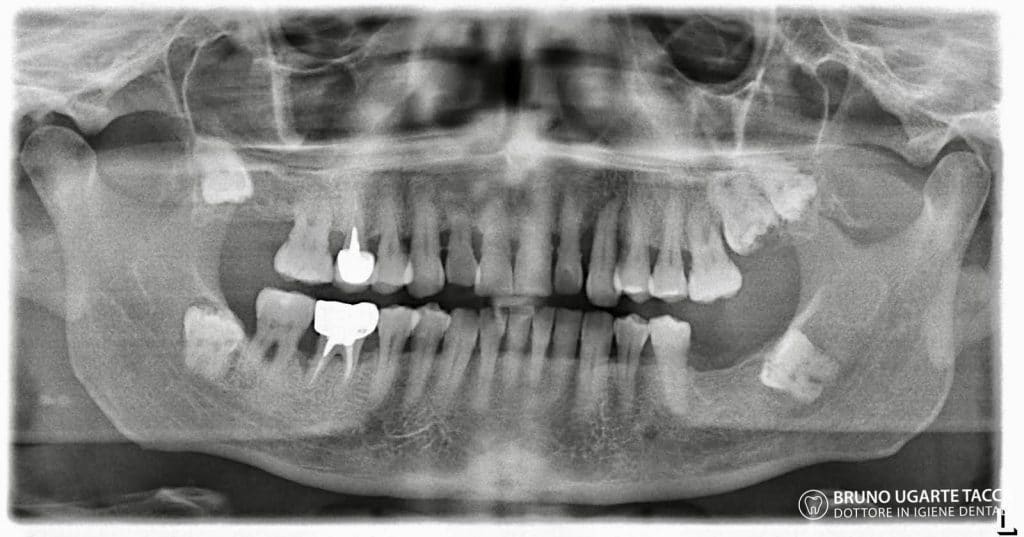

Performing the complete instrumentation

supragingival and subgingival with ultrasonic and / or manual instruments in one

single session or in two sessions at most performed over 2 days